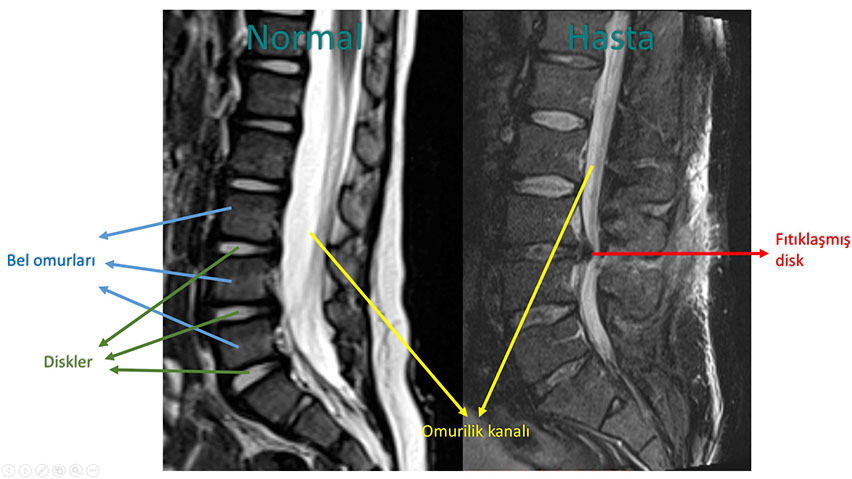

Yukardaki şekilde normal (solda) ile bel fıtığı olan bir hastanın (sağda) omurgalarının manyetik rezonans incelemeleri karşılaştırılmıştır. Filmleri incelerken yandan baktığımızı aklınızda tutun. Buna göre sağ taraftaki hastanın 3. ve 4. bel omurları arasındaki diskin bir parçasının yerinden çıkarak omurilik kanalına doğru yer değiştirdiğini ve bu bölgedeki sinirlere baskı yaptığını görebilirsiniz.